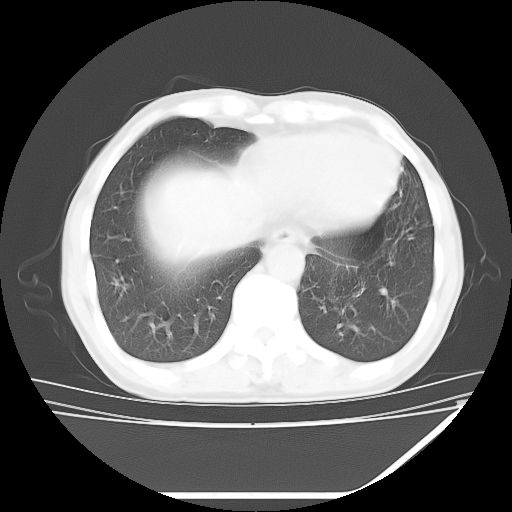

男,59岁,“结核性胸膜炎”30余年,胸部经常疼痛,多次x检查提示“肺部”炎症。腹部疼痛5日,b超提示:“肝内短管结石,余显示不清,建议进一步检查。”

两肺结核并右侧胸腔积液;脾脏、腹腔及腹膜后淋巴结结核[陈旧性];肝内胆管结石

胸部腹部都是结核(双肺。纵隔淋巴结,肝脏,脾脏,肠系膜)

均为结核所致,右侧少量胸腔积液